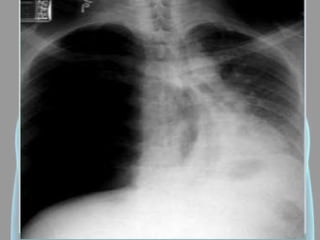

Derrame Pleural

• Hipotransparência;

• Denso e homogêneo;

• Em PA quando possuir

mais de 300ml;

• Em Laurell em

quantidades <300ml;

• Desvio do mediastino

para o lado oposto;

• Velamento do seio

costofrênico.

Derrame Pleural • Hipotransparência; •Denso e homogêneo; • Em PA quando possuir mais de 300ml; • Em Laurell em quantidades <300ml; • Desvio do mediastino para o lado oposto; • Velamento do seio costofrênico.